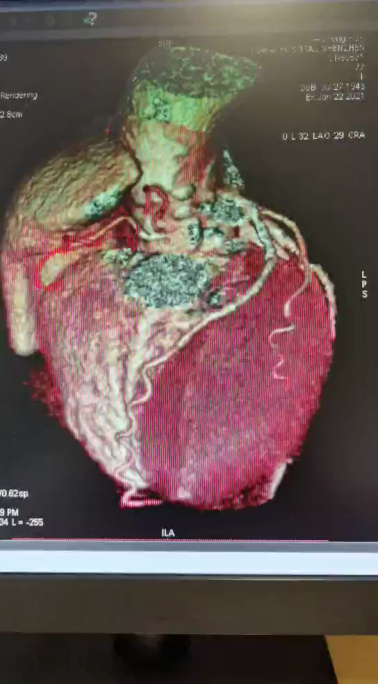

合并有严重的冠状动脉疾病、左锁骨下动脉严重钙化性狭窄、主动脉及分支严重钙化(也称为“瓷化”),搭桥手术风险也很高。

左主干钙化病变,主动脉严重钙化(也称为“瓷化”),外科搭桥风险高;左锁骨下动脉严重钙化性狭窄,如果不预先处理,后续外科手术时可能会影响脑循环......